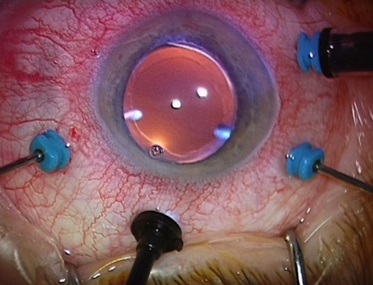

Витрэктомия (вид со стороны хирурга)

И самое интересное то, что картинка, которую видит хирург получается в перевернутом «вверх ногами» виде и реально не существует – это мнимое изображение, висящее между глазом и системой линз. Поэтому витреоретинальные хирурги учатся видеть такие образы и фокусироваться на них, а для «переворота» изображения существуют система инвертирования, которая подключается по запросу.

В некоторых случаях при работе удобнее работать с прямыми контактными линзами, установленными прямо на поверхность роговицы, например при работе в центральных областях роговицы – тогда изображение получается прямым и истинным.

Работа через контактную линзу